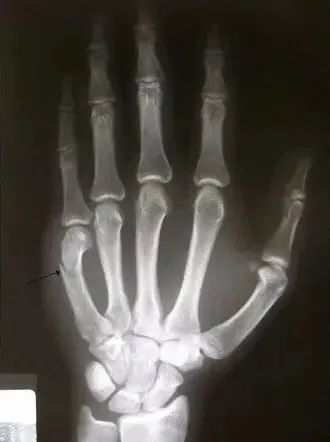

中手骨骨折の症状・病態・治療法についてご説明します。 特長 女性ホルモンと手の疾患について 環指と小指に中手骨骨折を受傷することが多く、レントゲン検査で中手骨の遠位(先端側)が折れて、偏位していることが確認できます。薬指や小指の中手骨骨折に最も発生しやすいが、強い衝撃が加わった場合には人指し指や中指にも起こる ことがあります。 中手骨骨折の症状 中手骨骨幹部骨折 手の甲の腫れ・痛み・骨折による骨のねじれ・手の変形・腫れ痛みによる可動域の制限 小指の付け根部分の突き指は症状が軽度と感じたとしても骨折しているケースは多いです。 また上記でも解説した 成長に関与する骨端線を含んだ骨折であることが多く、 正しい対処が行われないとケガをしてしまった指だけが 曲がってしまったり、短く

以前に手関節部の骨折をしています。 最近になり 小指(手の甲、手のひら側の両方とも)とくすり指(手の甲、ひら側の両方で小指側の半分)にしびれと痛み が出てきました。 手首をよく使う仕事をしています。 また趣味が自転車で、長時間のサイクリングで、ハンドルの手関節部への圧迫 手首の小指側が痛い時には以下の内容が考えられます。 TFCC損傷 手関節捻挫 骨折 手首を小指方向に曲げると小指側が痛いということで、 私は最初TFCC損傷を疑いました。 そもそもTFCCとは? TFCC損傷は手首の小指側にある組織が痛くなる症状です。 TCFF ボクサー骨折、中手骨骨幹部骨折、ベネット骨折に分類される|中手骨骨折の症状・原因・治療などについての基礎情報を掲載しています。 薬指や小指の中手骨に起きやすい 中手骨骨折は、手の骨折の一種です。中手骨と呼ばれる、手のひらや手の甲

手部骨折 醫學影像學習園地